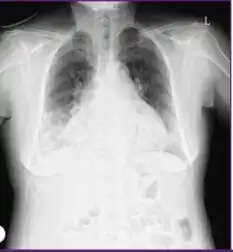

HMPV is associated with 5% to 40% of respiratory tract infections in hospitalized and outpatient children.[22][23] The virus is distributed worldwide and, in temperate regions, has a seasonal distribution generally following that of RSV and influenza virus during late winter and spring.[22][24] Serologic studies have shown that by the age of five, virtually all children worldwide have been exposed to the virus.[2][25][26][27] Despite near universal infection during early life, reinfections are common in older children and adults.[22][28][26][29] Human metapneumovirus may cause mild upper respiratory tract infection (the common cold). However, premature infants,[30] immunocompromised persons,[31][32][33][34] and older adults >65 years [29][35][36] are at risk for severe disease and hospitalization. In some studies of hospitalizations and emergency room visits, HMPV is nearly as common and as severe as influenza in older adults.[29][35][36][37] HMPV is associated with more severe disease in people with asthma[38][39][40][41] and adults with chronic obstructive pulmonary disease (COPD).[42][43][44] Numerous outbreaks of HMPV have been reported in long-term care facilities for children and adults, causing fatalities.[45][46][47][48][49]